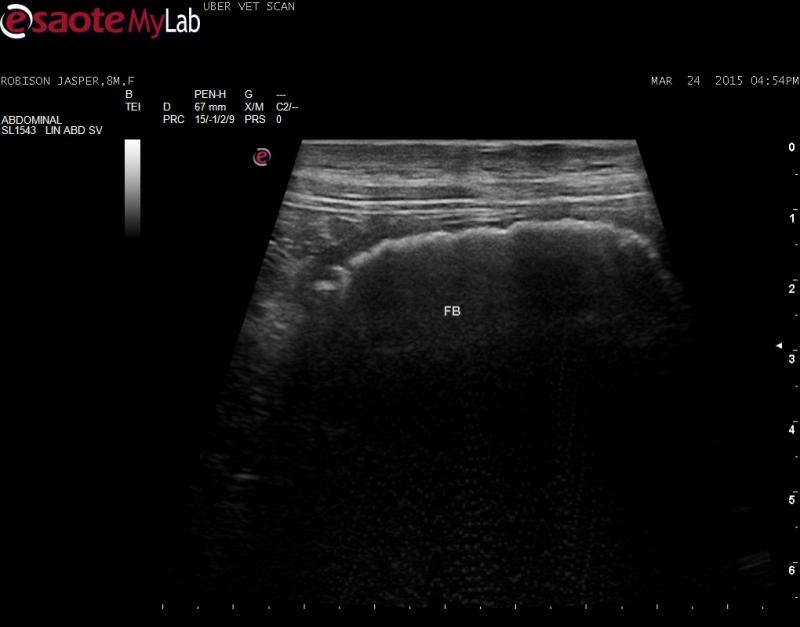

I believe there is a GI FB present in the SI; the stomach had a small amount of fluid in it, duodenum was normal. Strongly shadowing object found in loop of SI with surrounding hyperechoic fat. I have recommended surgery, but just want an opinion to confirm my findings – always afraid I am looking at the colon, but this looks like SI to me

Highly indicative of an intestinal FB. Murmur most likley physiological but monitor it.

FB confirmed at surgery.  I

FB confirmed at surgery.  I have added the photos before and after – mouse toy.

Fluid absorbing FB so not big

Fluid absorbing FB so not big dilation evident prior to the fb. The second video has perserosal fat inflammation so makes it an emergency.